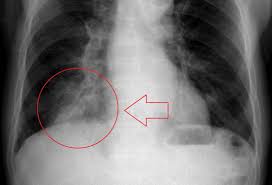

Non Small Cell Lung Cancer Nsclc Practice Essentials Background Pathophysiology

Non Small Cell Lung Cancer Nsclc Practice Essentials Background Pathophysiology from img.medscapestatic.com